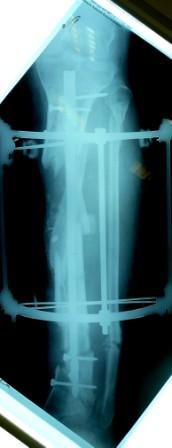

- Была выполнена репозиция в аппарате (рис1)

Имя     : Рис 1 После репозиции перед переходом на Штифт (1).JPG

Тип     : image/jpeg

Размер  : 20022 байтов

Описание: отсутствует

Url     : http://weborto.net:8080/pipermail/ortho/attachments/20090405/a3dc024e/attachment-0011.jpeg

Имя     : Рис 1 После репозиции перед переходом на Штифт (2).JPG

Размер  : 17201 байтов

Url     : http://weborto.net:8080/pipermail/ortho/attachments/20090405/a3dc024e/attachment-0012.jpeg